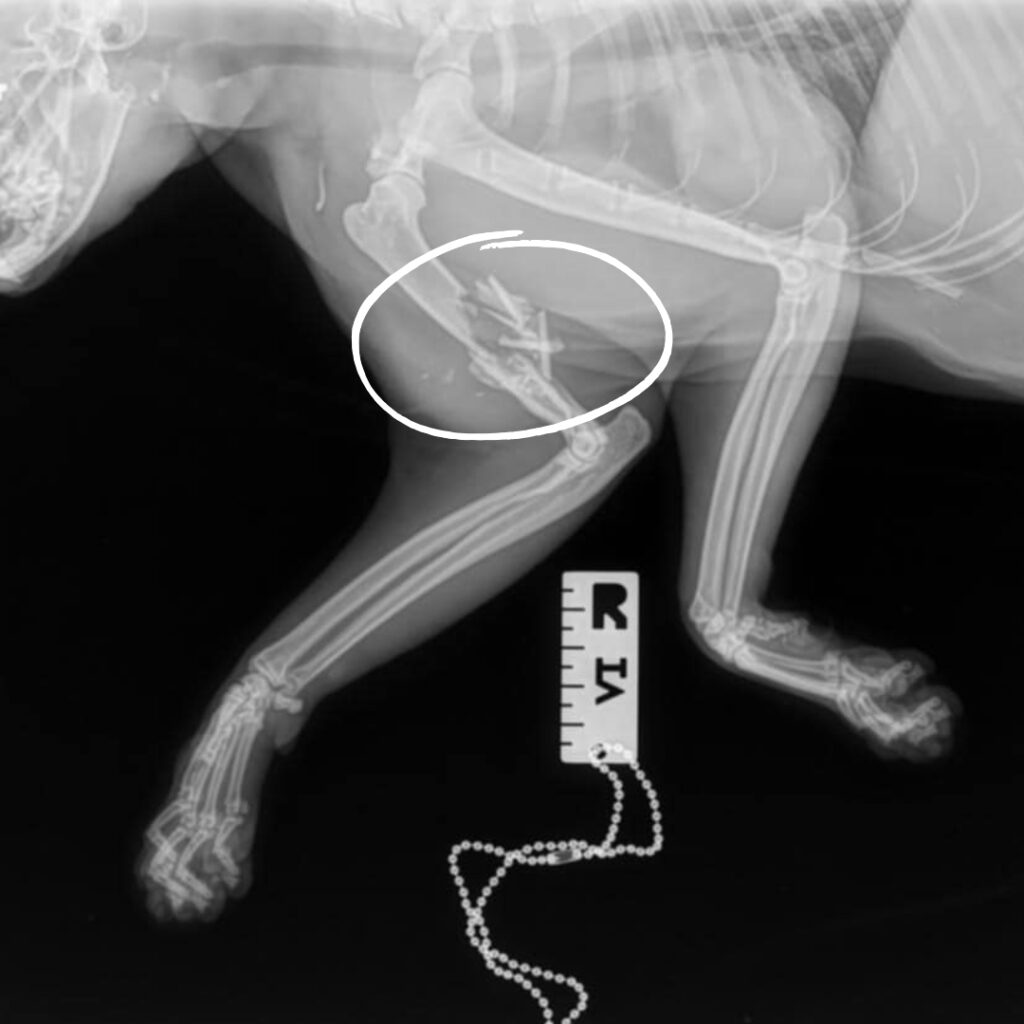

Poe arrived at KHS last week with extreme injuries caused by a gunshot. We jumped into action upon his arrival by providing him with pain medication and antibiotics to keep him comfortable as we assessed his wounds. Our hearts broke when x-rays revealed a severe break to Poe’s front right leg along with bullet and bone fragments littering his little body. The trauma he must have endured is unthinkable.

Poe, a two-year-old black cat, arrived at our Sam Swope Pet Treatment and Lifesaving Center this week with heartbreaking injuries caused by a gunshot. X-rays revealed this poor kitty’s front right leg was severely wounded, and his humerus bone was shattered by a bullet. Shrapnel litters his body and is even lodged behind his left eye. We can’t imagine the cruelty this sweet cat endured.

Our team is providing Poe with pain medication and antibiotics to keep him comfortable and infection-free while he heals. We’ve splinted his leg and hope his injuries will heal with time and rest. However, Poe will need to remain under observation so we can determine if an amputation surgery is needed. For now, we are grateful that this loving cat came to KHS where he is receiving the tender loving care he desperately needs and deserves. Please to support lifesaving, emergency medical care for vulnerable animals like Poe. Together, we can stand behind every broken, abused and neglected animal who comes through our doors.